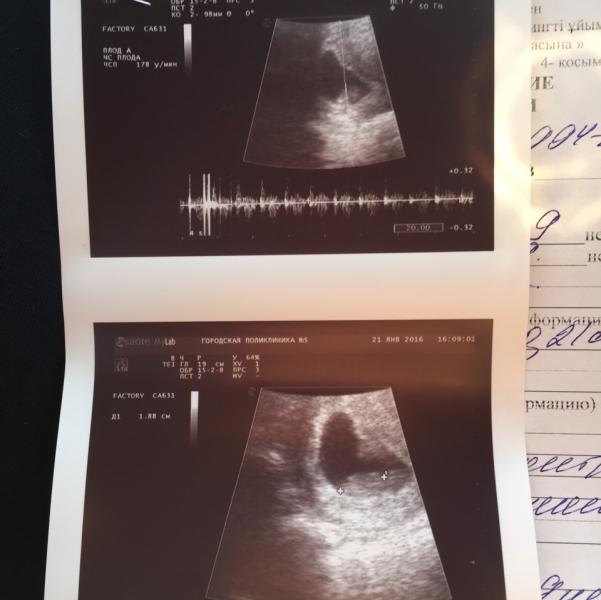

Увидели, услышали малыша, Слава Аллаху все хорошо, поставили 8-9 недель))